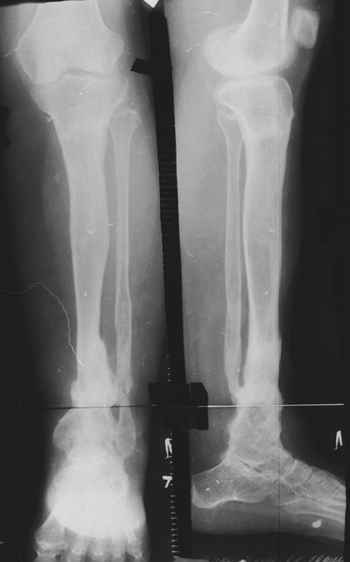

Глубокоуважаемые коллеги женщины! Поздравляем с праздником ВЕСНЫ, Международным женским днем - 8- МАРТА, здоровья , благополучия и успехов во всем! Ребенок 1г, мальчик, от первой беременности, родился без патологии весом 4кг, родители травму исключают, постепенно заметили деформацию н/з голени, которая начала увеличиваться . Брак родственный. Об-но; имеется угловая деформация открытым углом кзади на уровне н/з голени, ригидная , коррекции поддается мало. Функция коленного и г/с суставов не нарушены. Уважаемые детские ортопеды! Почему такое упорное молчание ортопедов! Я искреннее прошу прошения , если можно , мы нуждаемся в Ваших советах! План лечения; этапное, дистракционный аппарат, коррекция деформации, остеотомия в/з б/б кости, удлиняющая дистракция в обл остеотомии с одновременной компрессией в обл псевдоартроза и наблюдение , дальше по обстоятельству Вопросы; . 1. В каком возрасте можно начинать лечение, какие еще варианты лечения? 2. На Р-грамме как будто имеется недоразвитие дистального эпиметафиза м/берцовой кости, тогда что можно делать? С уважением Абдурашид.